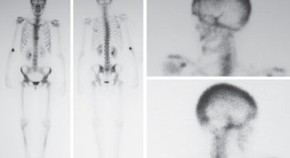

Lasting complete remission from widespread bone metastases is rare. The case of a 41-year-old premenopausal woman diagnosed with right-sided infiltrating ductal breast carcinoma andBRCA2mutation is described. She received high-dose anthracycline-based induction chemotherapy followed by autologous bone marrow transplantation with high-dose alkylator and platin-based conditioning regimens. The authors comment on the reasons for this unusual and sustained complete remission from widely metastatic breast cancer and the patient-specific factors that may have contributed to this outcome.